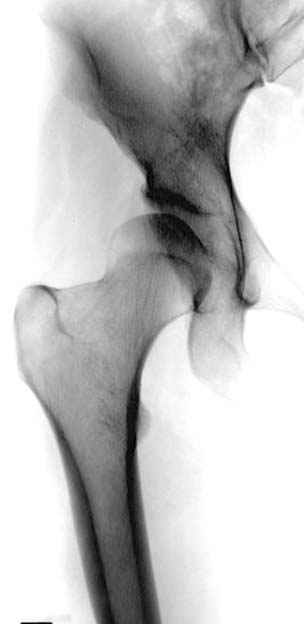

До операции #1

№ 1-3 до операции